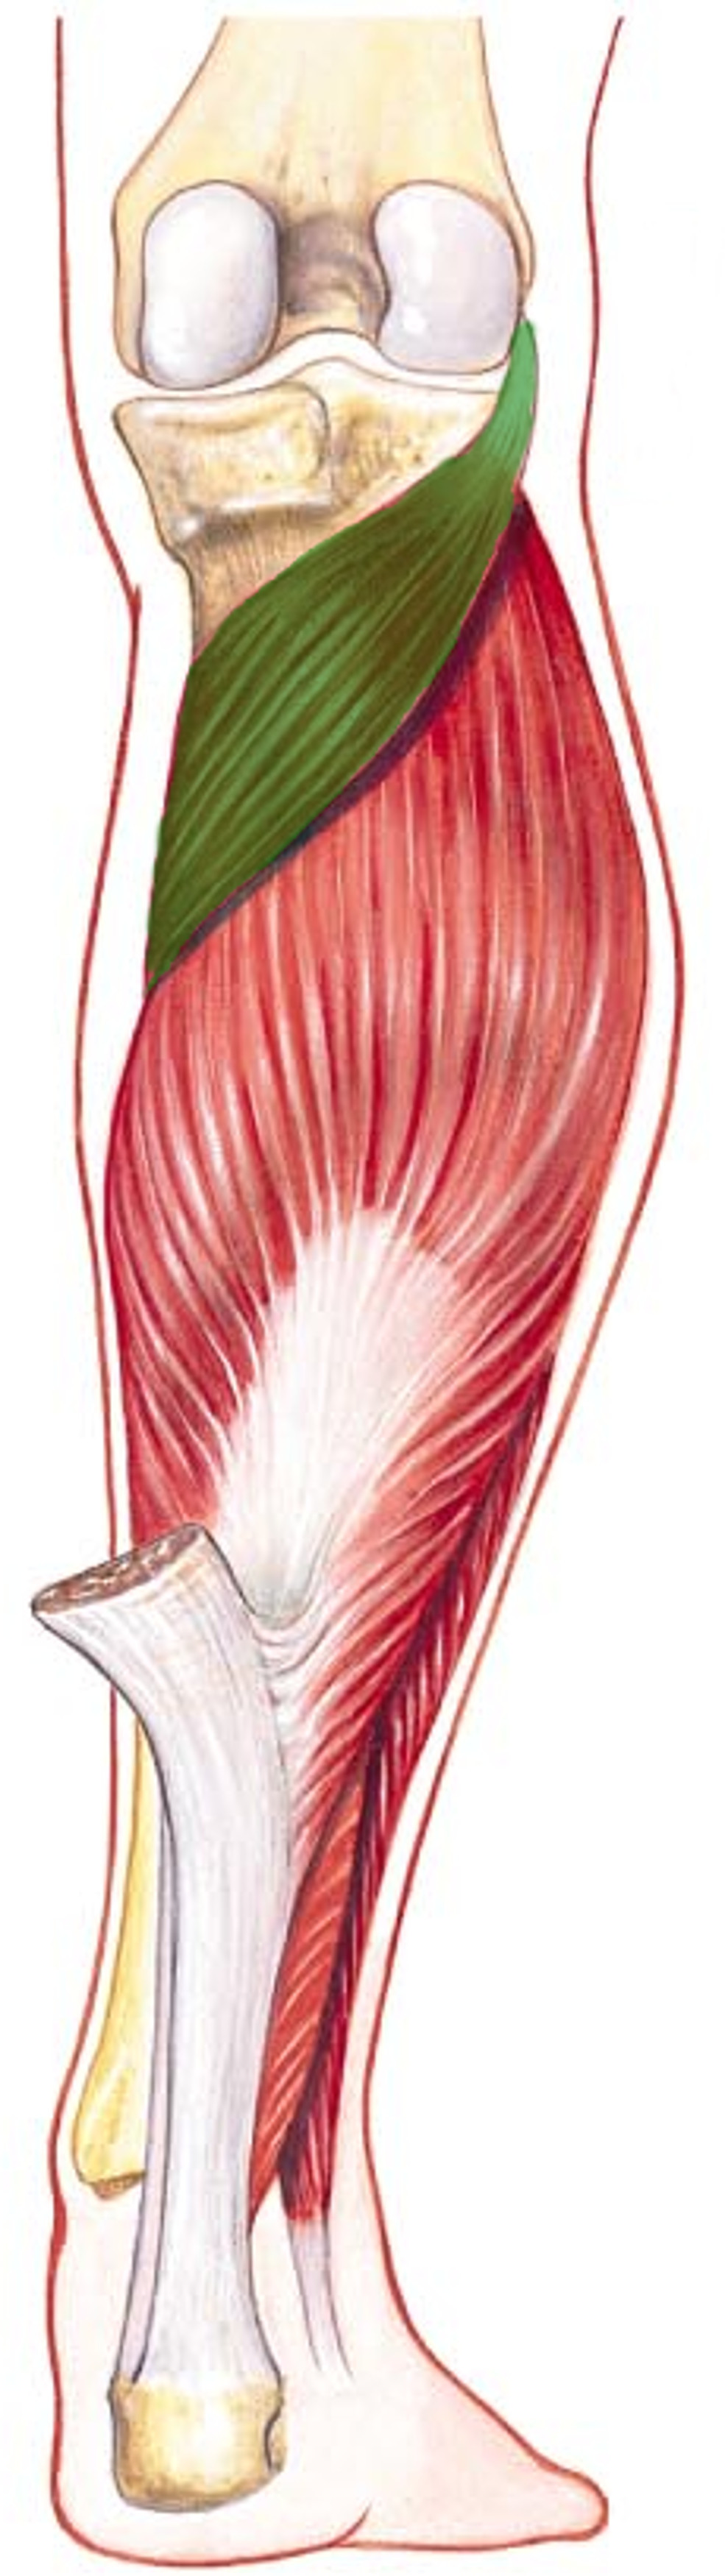

What is the innervation of this muscle?

Muscle - Popliteus

Tibial nerve

What is the innervation of this muscle?

Muscle - Rectus femoris

Femoral nerve L2-L4

Muscle - Quadraceps: Vastus lateralis

Femoral nerve